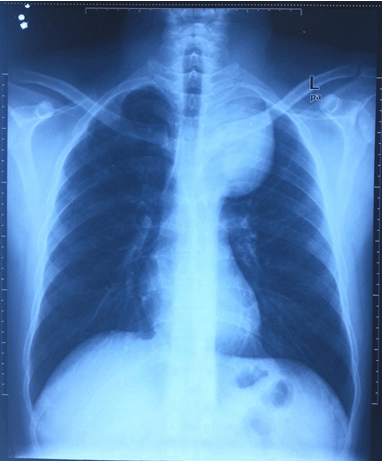

A 44-year-old asymptomatic male with no contributory medical history was incidentally detected to have superior mediastinal widening on chest X-ray (Figure 1) conducted for routine medical examination as an administrative requirement. He was further evaluated by thorax computed tomography (CT) scan (Figure 2) which was suggestive of a large mass in posterior aspect of superior mediastinum extending into left hemithorax, 8.9 x7.4x9.4 cm in dimensions, with areas of calcification and fat attenuation within. The mass was abutting left subclavian vessels and left brachiocephalic vein. Posteriorly, it was overlying medial aspect of 2nd to 5th ribs and vertebral bodies; medially it was abutting and mildly displacing esophagus and trachea with preserved fat planes; and inferiorly it was abutting arch of aorta. Subcentimeter lymph nodes were detected in pretracheal, precarinal and subcarinal regions. His routine hemogram and biochemical parameters were within normal range of reference and his metastatic workup was negative. Clinically, he did not have any symptom suggestive of myasthenia gravis or any paraneoplastic syndrome. He underwent CT Guided FNAC and Tru-Cut biopsy but results were inconclusive and non-contributory. Based on the imaging findings, a clinical diagnosis of mediastinal tumor was made.

Figure 1: Chest X-ray showing superior mediastinal widening.

X-ray chest generally shows a nonspecific broadened mediastinum and need further evaluation. Computed tomography is considered as the imaging modality of choice to characterize a mediastinal mass with regard to its local extent, invasion of adjacent structures, and to rule out distant metastases [4]. The major role of the magnetic resonance image seems to lie in its value for surgical planning and to rule out invasion of neighboring structures such as the great vessels or the heart, as well as in differentiating thymic lymphoid hyperplasia from thymoma by using chemical-shift sequences. Positron emission tomography CT scan is not helpful in distinguishing early from advanced thymoma but can be used to differentiate thymic carcinoma from thymoma [4] [9].